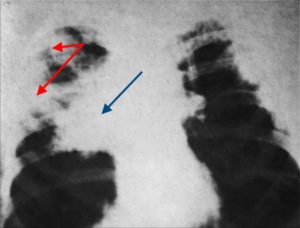

Рентгенологические данные могут иметь определенные различия и зависят от формы и стадии болезни:

- В стадии инфильтрации над поверхностью легких определяется снижение прозрачности легочного рисунка, затем плотность затенения возрастает, и становится виден инфильтрат неправильной формы с размытыми контурами и радиальной тяжистостью по периферии.

- Стадия абсцедирования характеризуется наличием очагов деструкции в пораженном легком с перифокальным воспалением и усилением легочного рисунка в здоровом легком.

- Нередко после прорыва абсцесса в паренхиме легких формируются плевролегочные полости с горизонтальным уровнем жидкости.

Рентгенологическое исследование в ранней стадии выявляет очаговые инфильтраты вокруг бронхов и сосудов, увеличение медиастинальных лимфатических узлов и содружественное поражение ребер или позвонков; характерно уплотнение плевры. Процесс может ограничиваться одним сегментом или захватывать целую долю. Течение болезни длительное, при отсутствии лечения развиваются кахексия и анемизация больных.